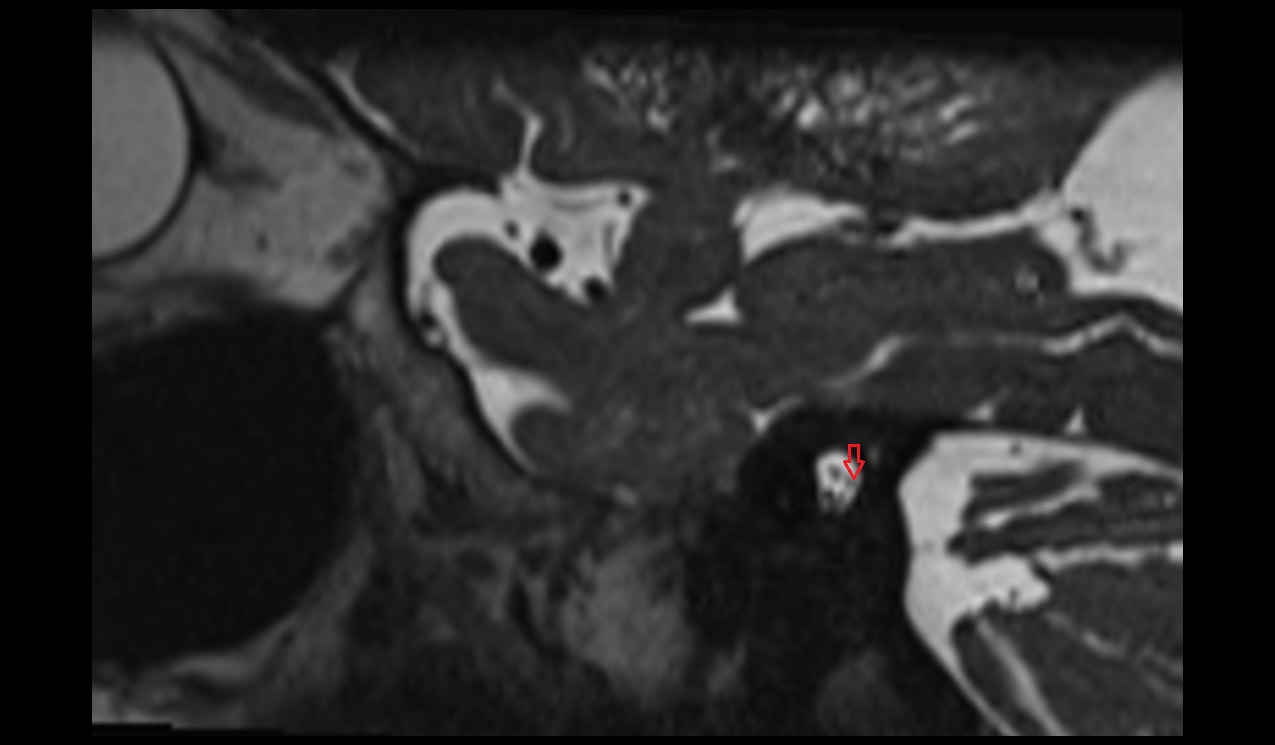

- Temporomandibular joint

- Mandibular condyle

- Mandibular fossa

- Lateral pterygoid muscle

- Masseter muscle

- Temporalis muscle